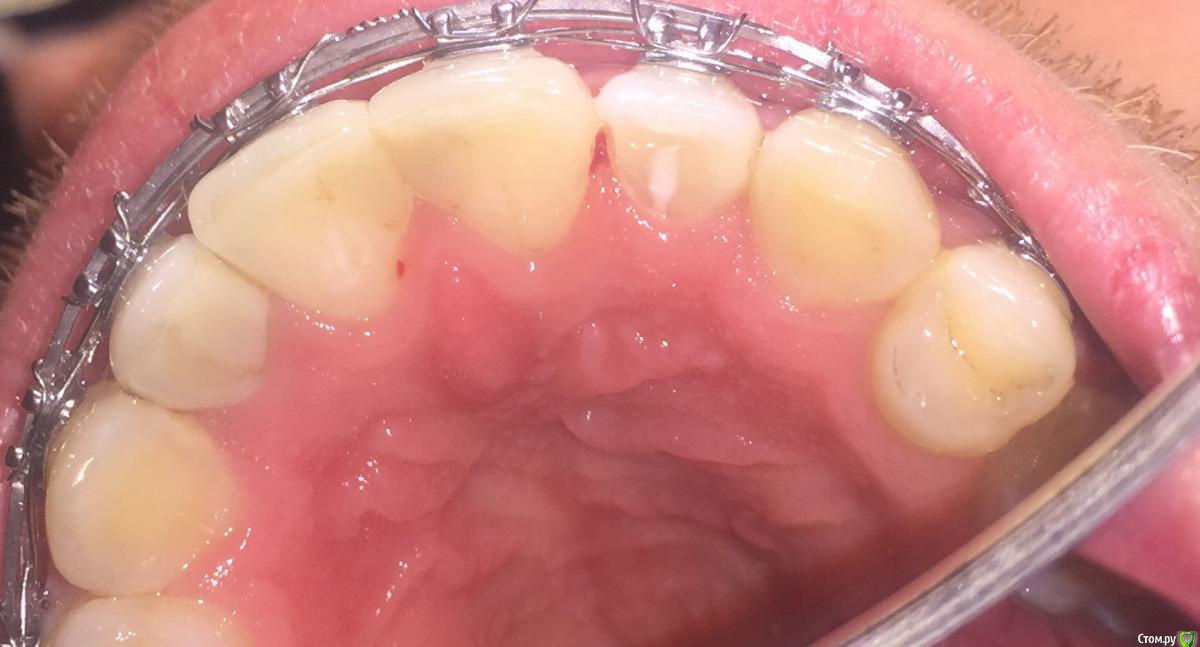

pedadva Опубликовано 22 ноября, 2018 Поделиться Опубликовано 22 ноября, 2018 Добрый день!9 месяцев назад была установлена пломбы на апроксимальный край 11 и 12 зуба.Обратился сейчас с жалобой на то, что зубная нить застревает под десной, выше сосочка 11 зуба и рвется.Врач по какой то причине стала сверить бором по апроксимале, теперь у меня так углубление и апроксимаьный контакт с небной стороны отсутствует. Мне это не нравится не эстетически ни функционально, боюсь за атрофию сосочка так как он висит сам по себе получается, не на контакте зубов.Могу ли я по вашему мнению просить восстановить контакт более плотный или я преувиличиваю?Спасибо! Ссылка на комментарий

pedadva Опубликовано 22 ноября, 2018 Автор Поделиться Опубликовано 22 ноября, 2018 (изменено) Надо дождаться окончания ортодонтического лечения и тогда оценить. В этом и проблема, что у меня все финал, ретейнер крепить нужно, а тут такая дыра. Вот фото До (на этой же неделе сделано) Изменено 22 ноября, 2018 пользователем pedadva Ссылка на комментарий